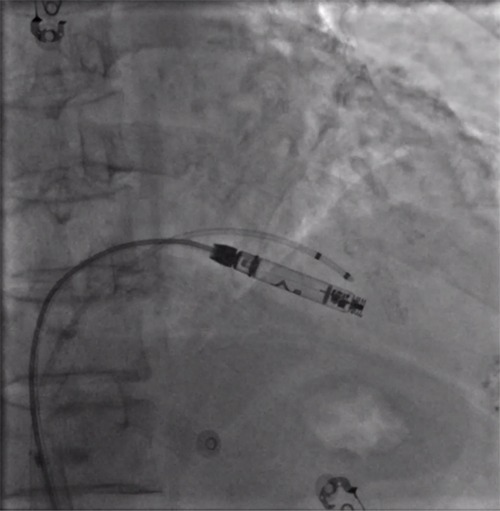

经过周密的术前准备,彭晖、孙志军两位主任带领邸北冰主治医师、柳晓娜主治医师和梁立丰医师在内的起搏电生理团队,于心脏介入手术室为患者实施手术。手术团队股静脉穿刺成功后,首先对下腔静脉进行造影并将外鞘放置送入下腔静脉,随后将新型主动固定螺旋无导线起搏器顺利跨瓣送入右心室目标位置,旋入前测试无导线起搏器各项电学参数良好,确认位置合适后旋入固定起搏器,在植入过程中动态测试起搏器各项参数以辅助判断固定程度,达到标准后进入对接栓模式,再次测试起搏器固定位置稳定、各项参数良好后释放起搏器,最后撤出鞘管,顺利完成手术。整个手术流程高效有序,医疗团队成员紧密配合,默契无间,仅耗时40分钟共同完成了这一具有挑战性的任务。

股静脉穿刺后下腔静脉造影

右室猪尾导管造影

RAO造影确认位置安全

LAO造影确认指向间隔部

电学标测参数良好,在此旋入1.5圈后进入对接栓模式,

摇摆与电学参数测试后释放起搏器